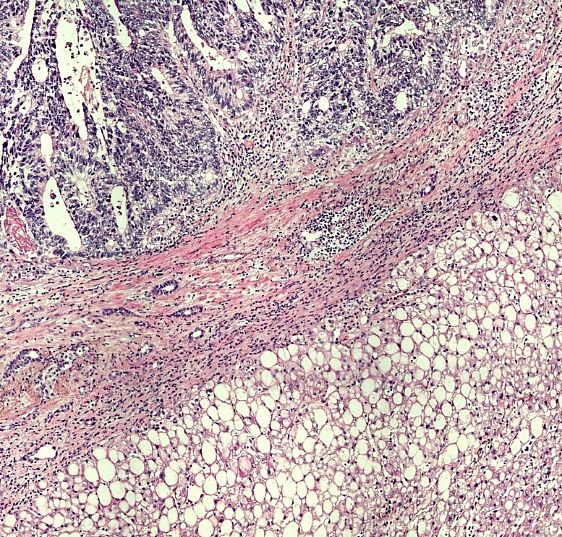

Colorectal cancer liver metastasis (CRCLM)

Interactive browser with the data from Andersson et al., 2024